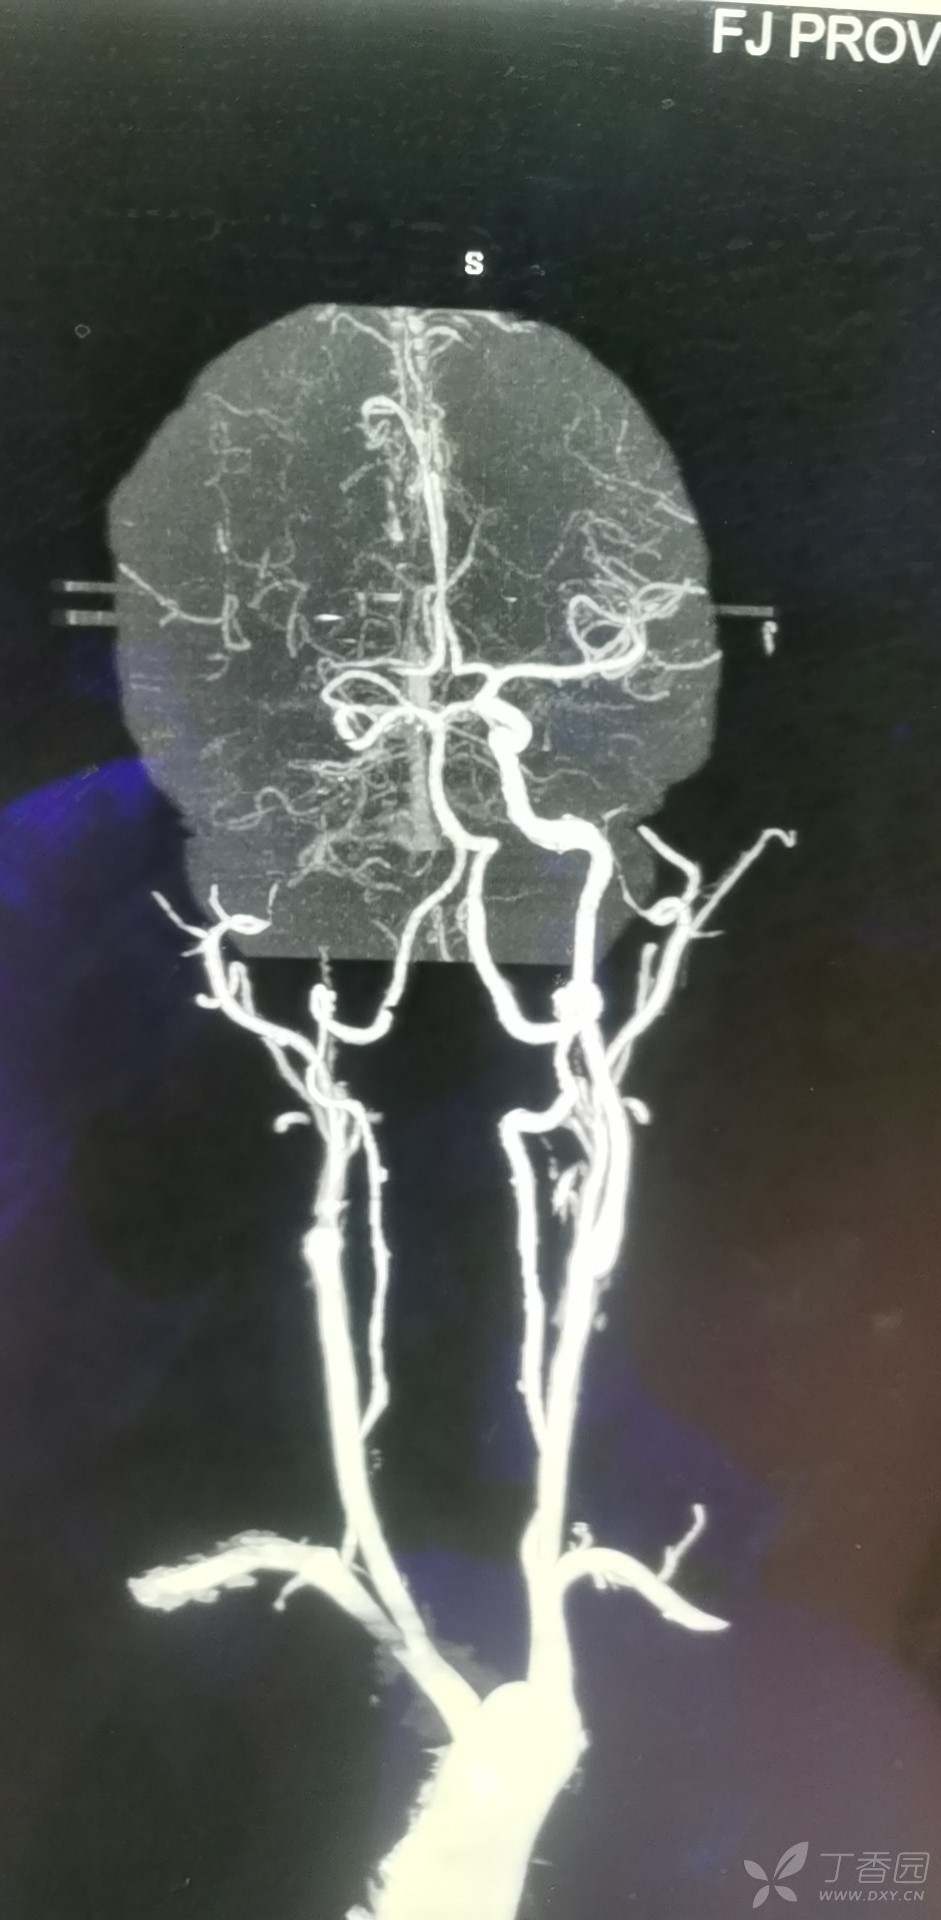

患者男性52岁,因咳嗽伴咯血,收入胸外,考虑咯血、肺部曲霉菌病曲菌病感等,1.8行支气管造影+病理血管栓塞术,1.22行胸腔镜下左下损毁肺叶切除术,术后恢复良好,2.4醒后卒中,双眼向右凝视,左侧肢体无力,行CTA提示右颈内闭塞,无房颤病史,

急诊介入下行脑血管腔内去栓术,术后取出血栓如下